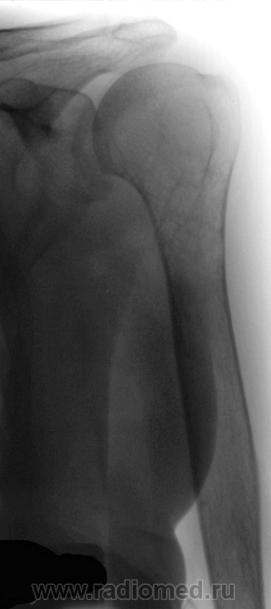

Нашей коллегой, Рыбаковой Людмилой Александровной, представлено интересное наблюдение - "Злокачественная остеообластокластома левой плечевой кости". Наблюдение в динамике - до - и после лечения.

ДО ЛЕЧЕНИЯ,